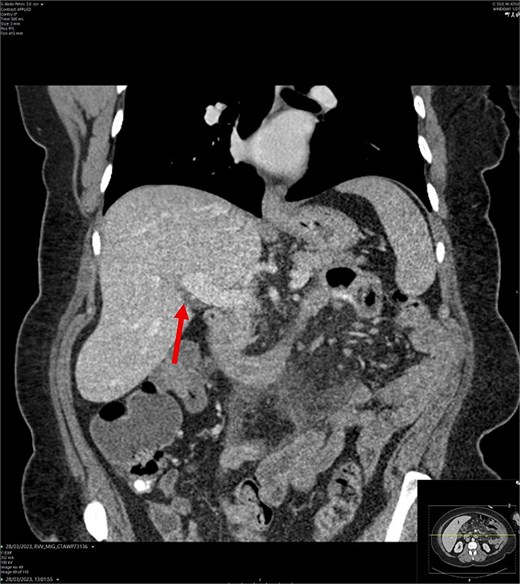

On admission, the patient’s blood tests showed normal inflammatory markers, liver function markers, and amylase (Table 1). The patient underwent an abdominal ultrasound scan, which did not visualize gallstones or the gallbladder. A computerised tomography (CT) abdomen-pelvis scan was done, and the gallbladder could not be visualized (Figs 1 and 2). Further investigations, which include a magnetic resonance cholangiopancreatography (MRCP) and hepatobiliary iminodiacetic acid (HIDA) scan, confirmed a gallbladder bud with an intact biliary tree (Figs 3–6). The patient denied a history of a cholecystectomy. She was diagnosed with gallbladder agenesis.

CT abdomen-pelvis scan in coronal view. The arrow points to where we expect the gallbladder to be seen, but it cannot be visualized on the scan.